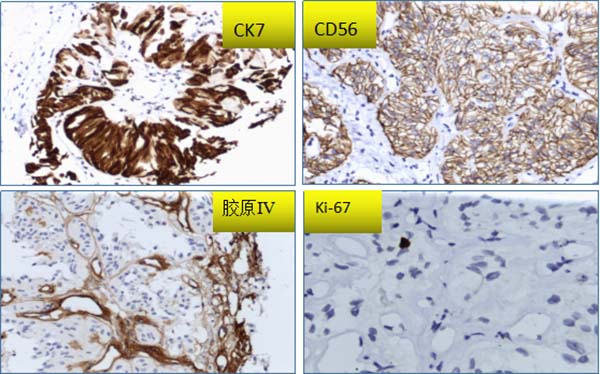

免疫组化结果:CK7、TTF-1、CD56、C117呈弥漫阳性,TG、Galectin-3呈灶状阳性,CK19、CT、CEA、CgA、S-100、MC、P63、TPO、Braf呈阴性,Ki67(SP6/MIB-1)胞膜/胞质均呈阴性,核增殖指数<1%,胶原Ⅳ显示透明变基底膜样物质阳性。

HTT通常表现为单侧单发有包膜的结节,界限清楚,切面实性、分叶状,灰白至淡黄色。镜下肿瘤以形成小梁状优势结构为特征,或呈实性巢状、腺泡状结构,间质富于窦状毛细血管;肿瘤细胞梭形或呈多角形,胞质丰富,嗜酸或透明,长轴垂直于基底膜,核的特征类似于PTC,核沟及核内假包涵体易见,核周可见特异性黄色小体,核分裂象罕见。瘤细胞巢间可见大量透明变的基底膜样物质沉积,PAS染色及胶原Ⅳ免疫组化染色阳性。HTT细胞核的特征与PTC有重叠,针吸细胞学易误诊为PTC,HTT细胞学示甲状腺滤泡上皮细胞丰富,围绕淀粉样透明变基质呈放射状排列,无乳头及滤泡结构,无平铺细胞片,细胞核拉长呈梭形,核膜不规则,核沟及核内假包涵体易见,胞界不清。Marina N. Nikiforova等研究表明,与PTC不同,GLIS重排在HTT中较普遍,特别是PAX8–GLIS3重排,这种融合基因导致GLIS过表达,进一步上调细胞外基质基因引起胶原沉积,从而产生镜下肿瘤组织中胶原丰富的现象。

Ki-67(MIB-1)染色瘤细胞质/细胞膜阳性在HTT较具有特异性,但并不是所有的HTT都会出现这种现象,本例Ki-67(MIB-1)细胞质/细胞膜染色呈阴性。